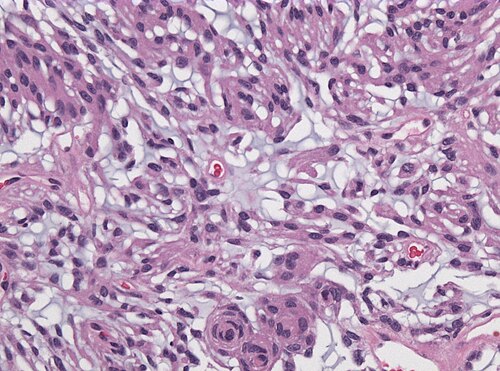

Provided clinical history

34 year old female with sudden seizures.

Site

Temporal lobe.

Intermediate magnification. H&E stain.

High magnification. H&E stain.

Differential diagnosis

Metastasis, Meningioma, Chordoid Glioma, Chordoma

The tumor has contact to the leptomeninges.

Spindle shaped in a mucoid background. Was EMA immunostain positive?

Diagnosis

Chordoid meningioma WHO grade II

Comment: Most meningioma subtypes correspond to WHO grade I. Chordoid meningioma is one of the variant that - even in absence of atypia or mitoses - is graded WHO II.